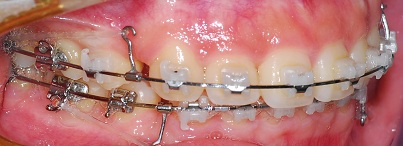

<옆면사진>

측면에서 보면 아직 입이 조금 나와잇져! 근데 정말 많이 들어갓어요ㅎㅎ